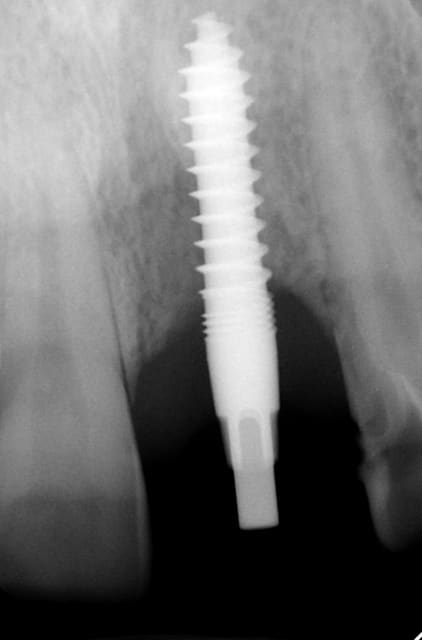

J'ai de tout en boutique..jeune homme 25 ans accident de piscine choc sur la bordure ( fêlure existante..fistule), extraction le jour même, temporisation 4 mois (avec un bout de trombone) Monobloc 16mm 60N, prep cap zircone droit 2/2 provisoire ion, temporisation 3 mois ceramo ceram..

J'ai de tout en boutique..jeune homme 25 ans accident de piscine choc sur la bordure ( fêlure existante..fistule), extraction le jour même, temporisation 4 mois (avec un bout de trombone) Monobloc 16mm 60N, prep cap zircone droit 2/2 provisoire ion, temporisation 3 mois ceramo ceram.. suite des photos :)

Au contraire..si tu regarde attentivement les radios tu veras qu'en quelques mois il y a une néoformation osseuse autour des micros spires. On voit un manque le jour de la pose et plus d'os avec la Procera. Volontairement j'ai pas plus enfoncé l'implant ..Si j'avais ouvert j'aurai bousillé tout le potentiel cicatriciel..Charon l'a démontré depuis longtemps en paro. Aux patient je leur explique que "Ouvrir c'est comme tondre le gazon avec un motoculteur" .

Donc il y maintien et renfort du parodonte.